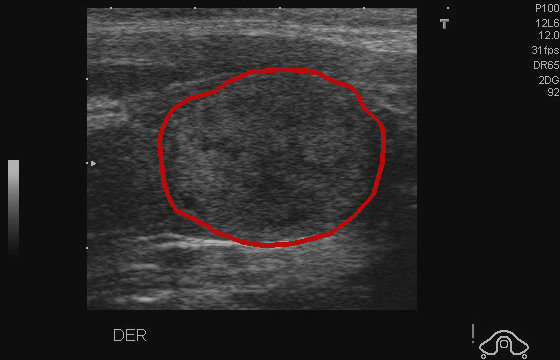

Object Movement

MRI OmniMedVQA Disease Diagnosis

Object Movement - L0 (Original)

L0

L0 (Original)

Object Movement - L1 (Moderate)

L1

L1 (Moderate)

Object Movement - L2 (Severe)

L2

L2 (Severe)

Question

What is the visual finding in this image?

A Rotator cuff tear B Plantar fascia pathology C Bunion D Golfer's elbow

Ground Truth: B. Plantar fascia pathology